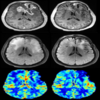

DSC MRI imaging is based on the principle that flow of a paramagnetic contrast agent through a capillary bed will transiently change the magnetic susceptibility of the given tissue. Decreased signal intensity on spin-echo or gradient-echo images after the first pass of the contrast agent, frequently described as susceptibility-induced T2* shortening, is the result of this temporal change in magnetic susceptibility. This signal time curve is then converted into a concentration time curve, and use of tracer kinetic analysis various hemodynamic variables, such as cerebral blood volume, cerebral blood flow, and mean transit time, as well as metrics that address vessel leakage may be estimated. Combined, these metrics enable microvascular imaging, providing a visual correlate of blood flow, volume, and vessel permeability.

• Estimation of quantitative parameters(rCBV,rCBF and MTT) from DSC MRI.

• Output RCBV image: Relative Cerebral Blood Volume (rCBV) map.

• Output RCBF image: Relative Cerebral Blood Flow (rCBF) map.

• Output MTT image: Mean Transit Time (MTT) map.